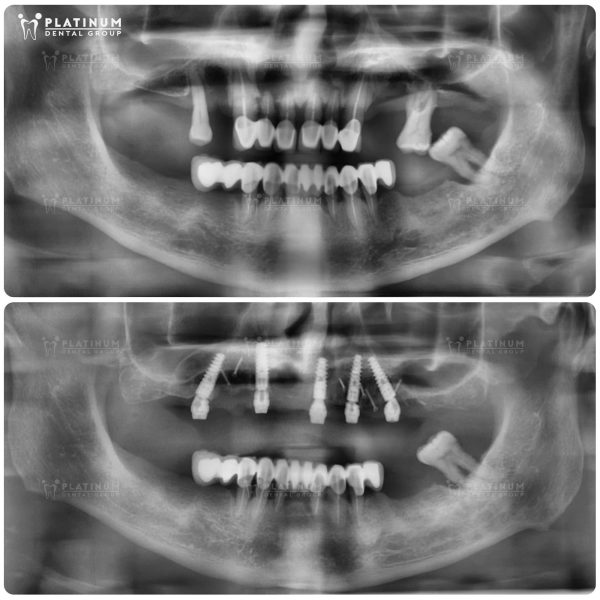

Hình ảnh trước và sau khi trồng Implant của Mr. James Harrison

Hành trình của Mr. James Harrison – đến từ Úc là minh chứng cho sức mạnh của công nghệ nha khoa hiện đại trong việc tái tạo nụ cười. Trước khi điều trị, Mr. James phải đối mặt với tình trạng răng mòn, sâu nặng và biến màu do viêm nhiễm kéo dài. Những chiếc răng cửa phía trước bị vỡ và tiêu xương nghiêm trọng, trong khi răng hàm trên và dưới gần như mất hết chức năng, khiến khả năng nhai và thẩm mỹ của anh bị ảnh hưởng lớn.

Sau khi được bác sĩ tại Platinum Dental Group thăm khám và lên kế hoạch điều trị, Mr. James đã lựa chọn phương pháp cấy ghép Implant toàn hàm với 6 trụ cho hàm trên và 6 trụ cho hàm dưới. Kết quả đạt được là một hàm răng trắng sáng, cân đối hài hòa với khuôn mặt, cùng khả năng nhai phục hồi hoàn toàn. Implant mang lại cảm giác chắc chắn, thoải mái như răng thật, giúp anh tự tin tận hưởng cuộc sống hàng ngày. Với quyết định bay từ Úc sang Việt Nam để điều trị, Mr. James đã thực sự tìm lại được nụ cười và sự thoải mái mà mình hằng mong muốn.